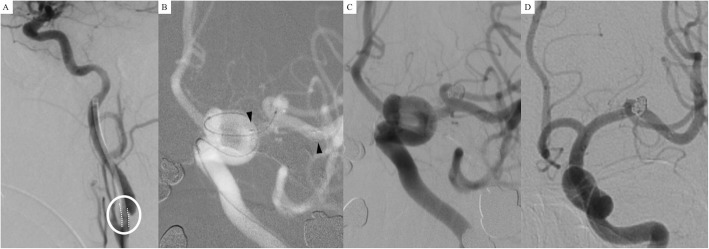

A 60-year-old woman experienced headaches, and a left middle cerebral artery aneurysm was diagnosed on MRA. She was willing to treat the lesion aggressively because of a family history of ruptured intracranial aneurysms. DSA revealed a middle cerebral artery aneurysm approximately 4.6 mm in maximal length with a neck size of 3.9 mm and carotid stenosis of about 40% in the left carotid bulb. For endovascular treatment of the aneurysm, a 5Fr-guiding catheter was placed in the left ICA, but it seemed to be stuck in the stenotic segment of the ICA (white dots inside of a white circle in Fig. 3a). A single microcatheter (pre-shaped Excelsior SL-10 45 degree) was steam-shaped into a “Z” shape and navigated to the left MCA. We deployed a Neuroform Atlas stent (3.0 mm × 15 mm) in left M1 (black arrowheads) and selected the aneurysm with the same microcatheter using the cell-through technique (Fig. 3b). A neck remnant resulted in the final angiography after coiling (Fig. 3c). On 6-month follow-up angiography, the aneurysm was completely occluded (Fig. 3d).

Fig. 3.

a A 5Fr-guiding catheter was placed in the left internal carotid artery (ICA) with stenosis of about 40% in the left carotid bulb. The guiding catheter seemed to be stuck in the stenotic segment of the ICA (white dots inside of a white circle). b A single microcatheter (pre-shaped Excelsior SL-10 45 degree) was steam-shaped into a “Z” shape and navigated to the left MCA. We deployed a Neuroform Atlas stent (3.0 mm × 15 mm) in the left M1 (black arrowheads) and selected the aneurysm with the same microcatheter using the cell-through technique. c A neck remnant was seen in the final angiography after coiling. (d) On 6-month follow-up angiography, the aneurysm was completely occluded